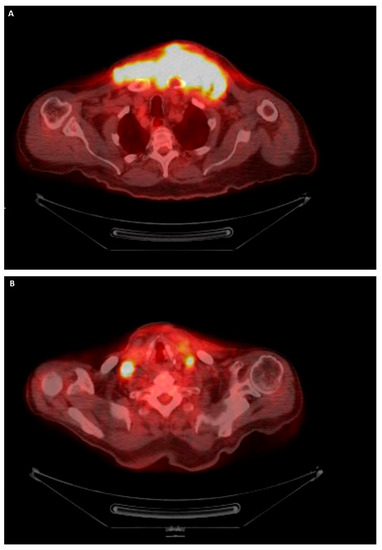

PET/CT of the whole body was performed to show how the neoplasm had grown to 15.2 cm (12 cm in the previous CT scan one month earlier, Figure 4A). Cervical and axillary lymphadenopathy was also observed (Figure 4B). The specimen was sent for molecular testing, which confirmed that the tumor harbored the BRAF V600E mutation. The patient died approximately six months after the primary pathological diagnosis.

Figure 4.

PET/CT imaging of the whole of the body. (A) Mediastinal mass. (B) Lymphadenopathy.